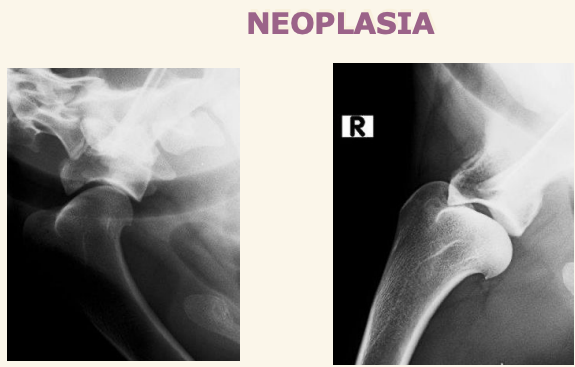

Neoplasias (Condrosarcoma y a veces osteosarcoma) son mas comunes. Neoplasias:

Los sarcomas aparecen lejos del codo en extermidades anteriores y cerca de la rodilla en extermidades posteriores.

Las neoplasias sueln ser en la zona proximal del humero